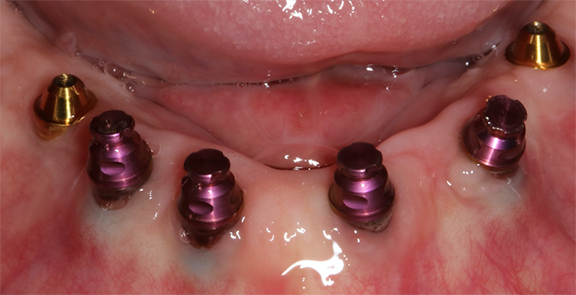

In the case demonstrated in Figure 32 through Figure 37, a maxillary prosthesis retained by six implants, three screw-retained and three retained with the novel fixed abutments, with no screws (to avoid screw-access holes emerging from the facial surface of the prosthesis) was fabricated for the patient. The novel fixed retentive abutments make it easier to maintain the prosthesis.41 The retentive inserts within the attachment housing should be replaced every time the prosthesis is removed. However, the procedure is quick and simple to accomplish.

Fig 33. Multiunit abutments (gold) were attached to the three implants, and the novel abutments would be attached to the other three implants.